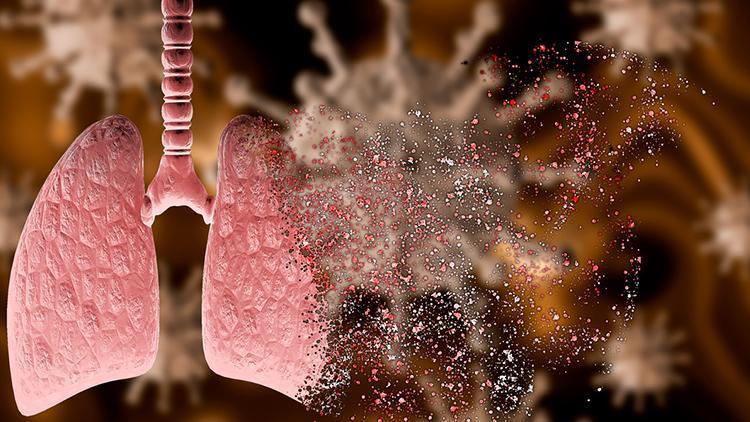

Covid-19 enfeksiyonu akciğer komplikasyonlarının gelişme riskinin KOAH hastalarında sağlıklı bireylerden daha yüksek olduğunun çalışmalarda gösterildiğini ve bu nedenle pandemi sürecinde hastalanmamak için korunma önlemlerine uyumun çok önemli olduğunu belirten Göğüs Hastalıkları Uzmanı Dr. Esra Sönmez, konuyla ilgili önemli bilgiler paylaştı.

KOAH’ta gerek bronş duvarlarındaki koruyucu bariyerlerdeki yıkım, gerekse akciğer dokusundaki hasar kişiyi enfeksiyonlara daha açık kılıyor ve gelişen enfeksiyonların iyileşme süreci de daha uzun oluyor. Covid-19 çalışmalarında, KOAH varlığının koronavirüs enfeksiyonun daha ağır ve daha ölümcül seyri için önemli bir risk faktörü olduğu gösterildi. Çalışmalarda 45 yaş üzeri, sigara içen KOAH’lı hastalarda ölüm oranları yüzde 55-60 düzeyinde.